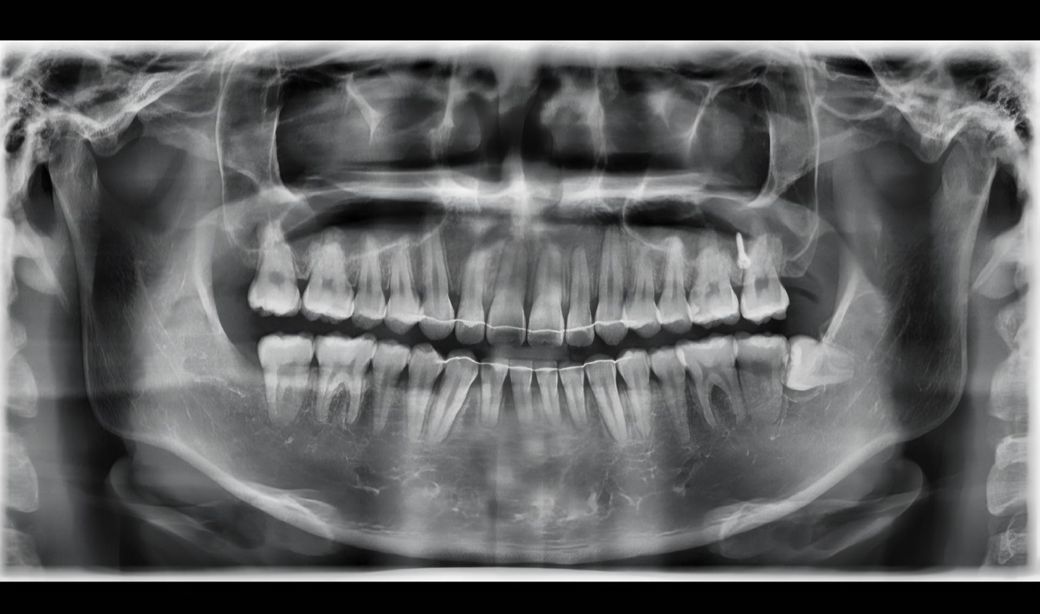

24년 초에 레진치료를 받았습니다

큰어금니 볼쪽옆면 레진치료하였습니다

(상악 오른쪽 2대구치)